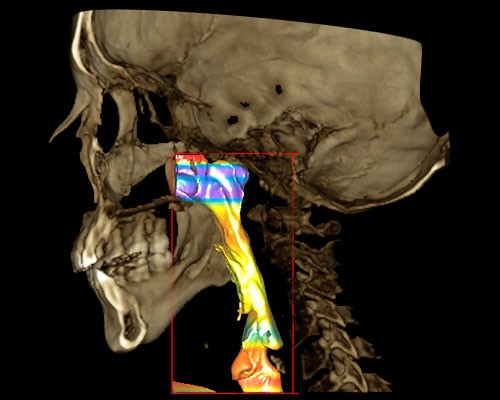

Exclusivo Sistema de Fotografía 3D disponible para todos nuestros clientes. IDM y Planmeca son pioneros en introducir este tipo de concepto en el Perú y consiste en la adquisición de una fotografía 3D sin necesidad de emitir radiación.